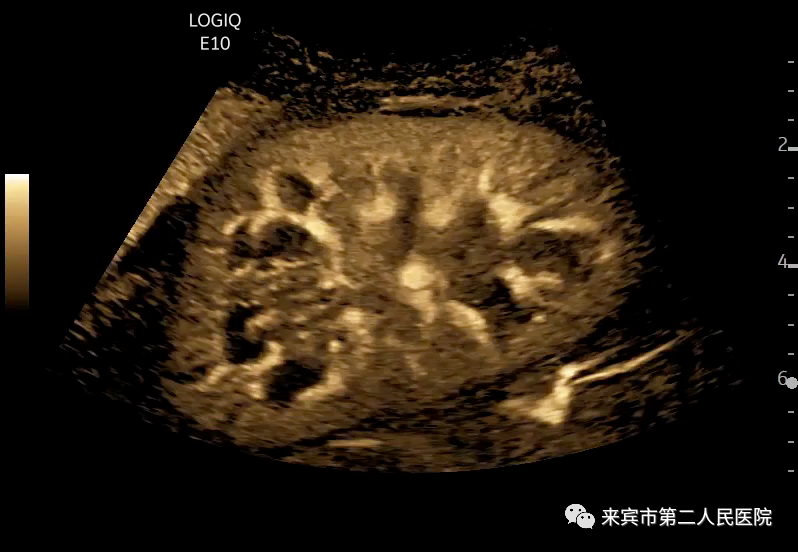

三、彩超在腹部检查中的应用:

彩超在腹部器官检查中应用范围最广,在腹部中除胃肠道,几乎所有的器官都可以检查。首先上腹部有肝脏、胆囊、脾脏、胰腺、胆总管等等。其次下腹部的器官主要是泌尿和生殖系统,有肾脏、膀胱、输尿管、前列腺、子宫、卵巢、输卵管和睾丸。通过彩超检查可以诊断器官的炎性病变、良恶性肿瘤,胆囊、膀胱、输尿管以及肾脏的结石,肝脏、脾脏、肾脏和卵巢的囊肿等等。